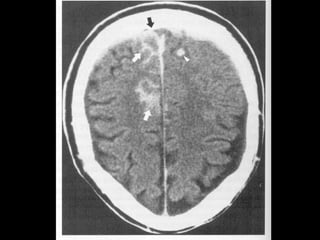

Traumatism cranio-cerebral prin împuşcare – hemoragie frontalăTraumatism cranio-cerebral prin împuşcare – hemoragie frontală

bilaterală, contuzie parietală şi hemoragie subarahnoidianăbilaterală, contuzie parietală şi hemoragie subarahnoidiană